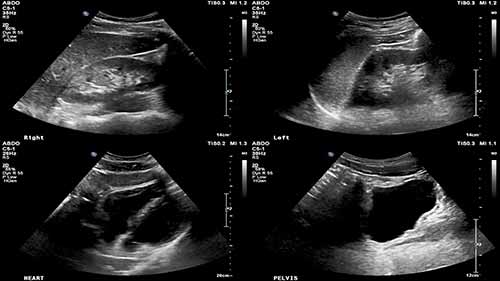

经食道超声心动图——图像获取

时长:9 分钟

类别:医学影像技术

简介:通过现场演示,来介绍经食道超声心动图的相关知识,涵盖了如何插入探头、如何移动探头,如何获取不同的超声图像等内容。

超声心动图——心尖四腔切面

在经胸回声上显示优化的心尖四腔图像,识别这些结构,并对其进行评估,判断它们是否正常。